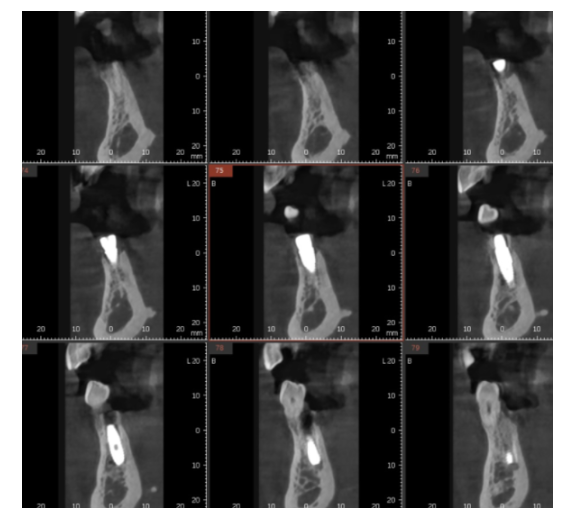

1)치조골 상태가 양호할 것

CT 촬영 결과 뼈 높이와 두께가 충분해야 하죠.

240429 수술까지 완료한 모습은 이렇습니다.